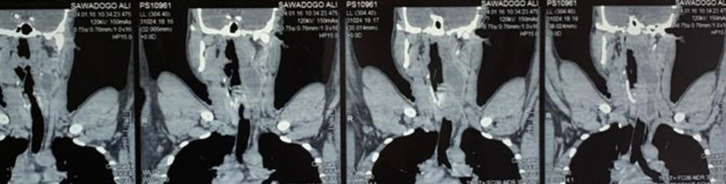

Observation: A 36-year-old black African patient of Burkinabè origin, with a history of tuberculosis infection (his mother had pulmonary tuberculosis) and no other pathological history, presented with chronic inflammatory cervicalgia that had been developing for six months in a non-febrile context of altered general condition. Examination showed a left latero-cervical swelling associated with a left basithoracic swelling, both fluctuant. Pleuropulmonary and neurological examinations were normal. HIV serology and tuberculin skin test were negative. Cervico-thoracic computed tomography revealed multiple abscesses. The abscesses were incised and drained. Analysis of the specimen showed the presence of acid-fast bacilli by direct examination and Mycobacterium tuberculosis by Xpert test, with sensitivity to rifampicine. The diagnosis was multiple tuberculous cold abscesses associated with cervical Pott's sore. The patient was started on standard analgesics and antituberculosis drugs for 12 months. The course was favorable, with a follow-up of one year after treatment.